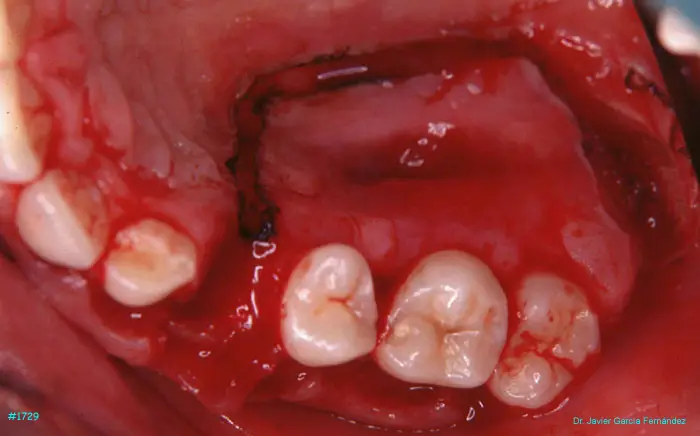

Atlas of Surgical Techniques in Periodontics. Chapter IV. Atlas de Técnicas Quirúrgica en Periodoncia

image 237